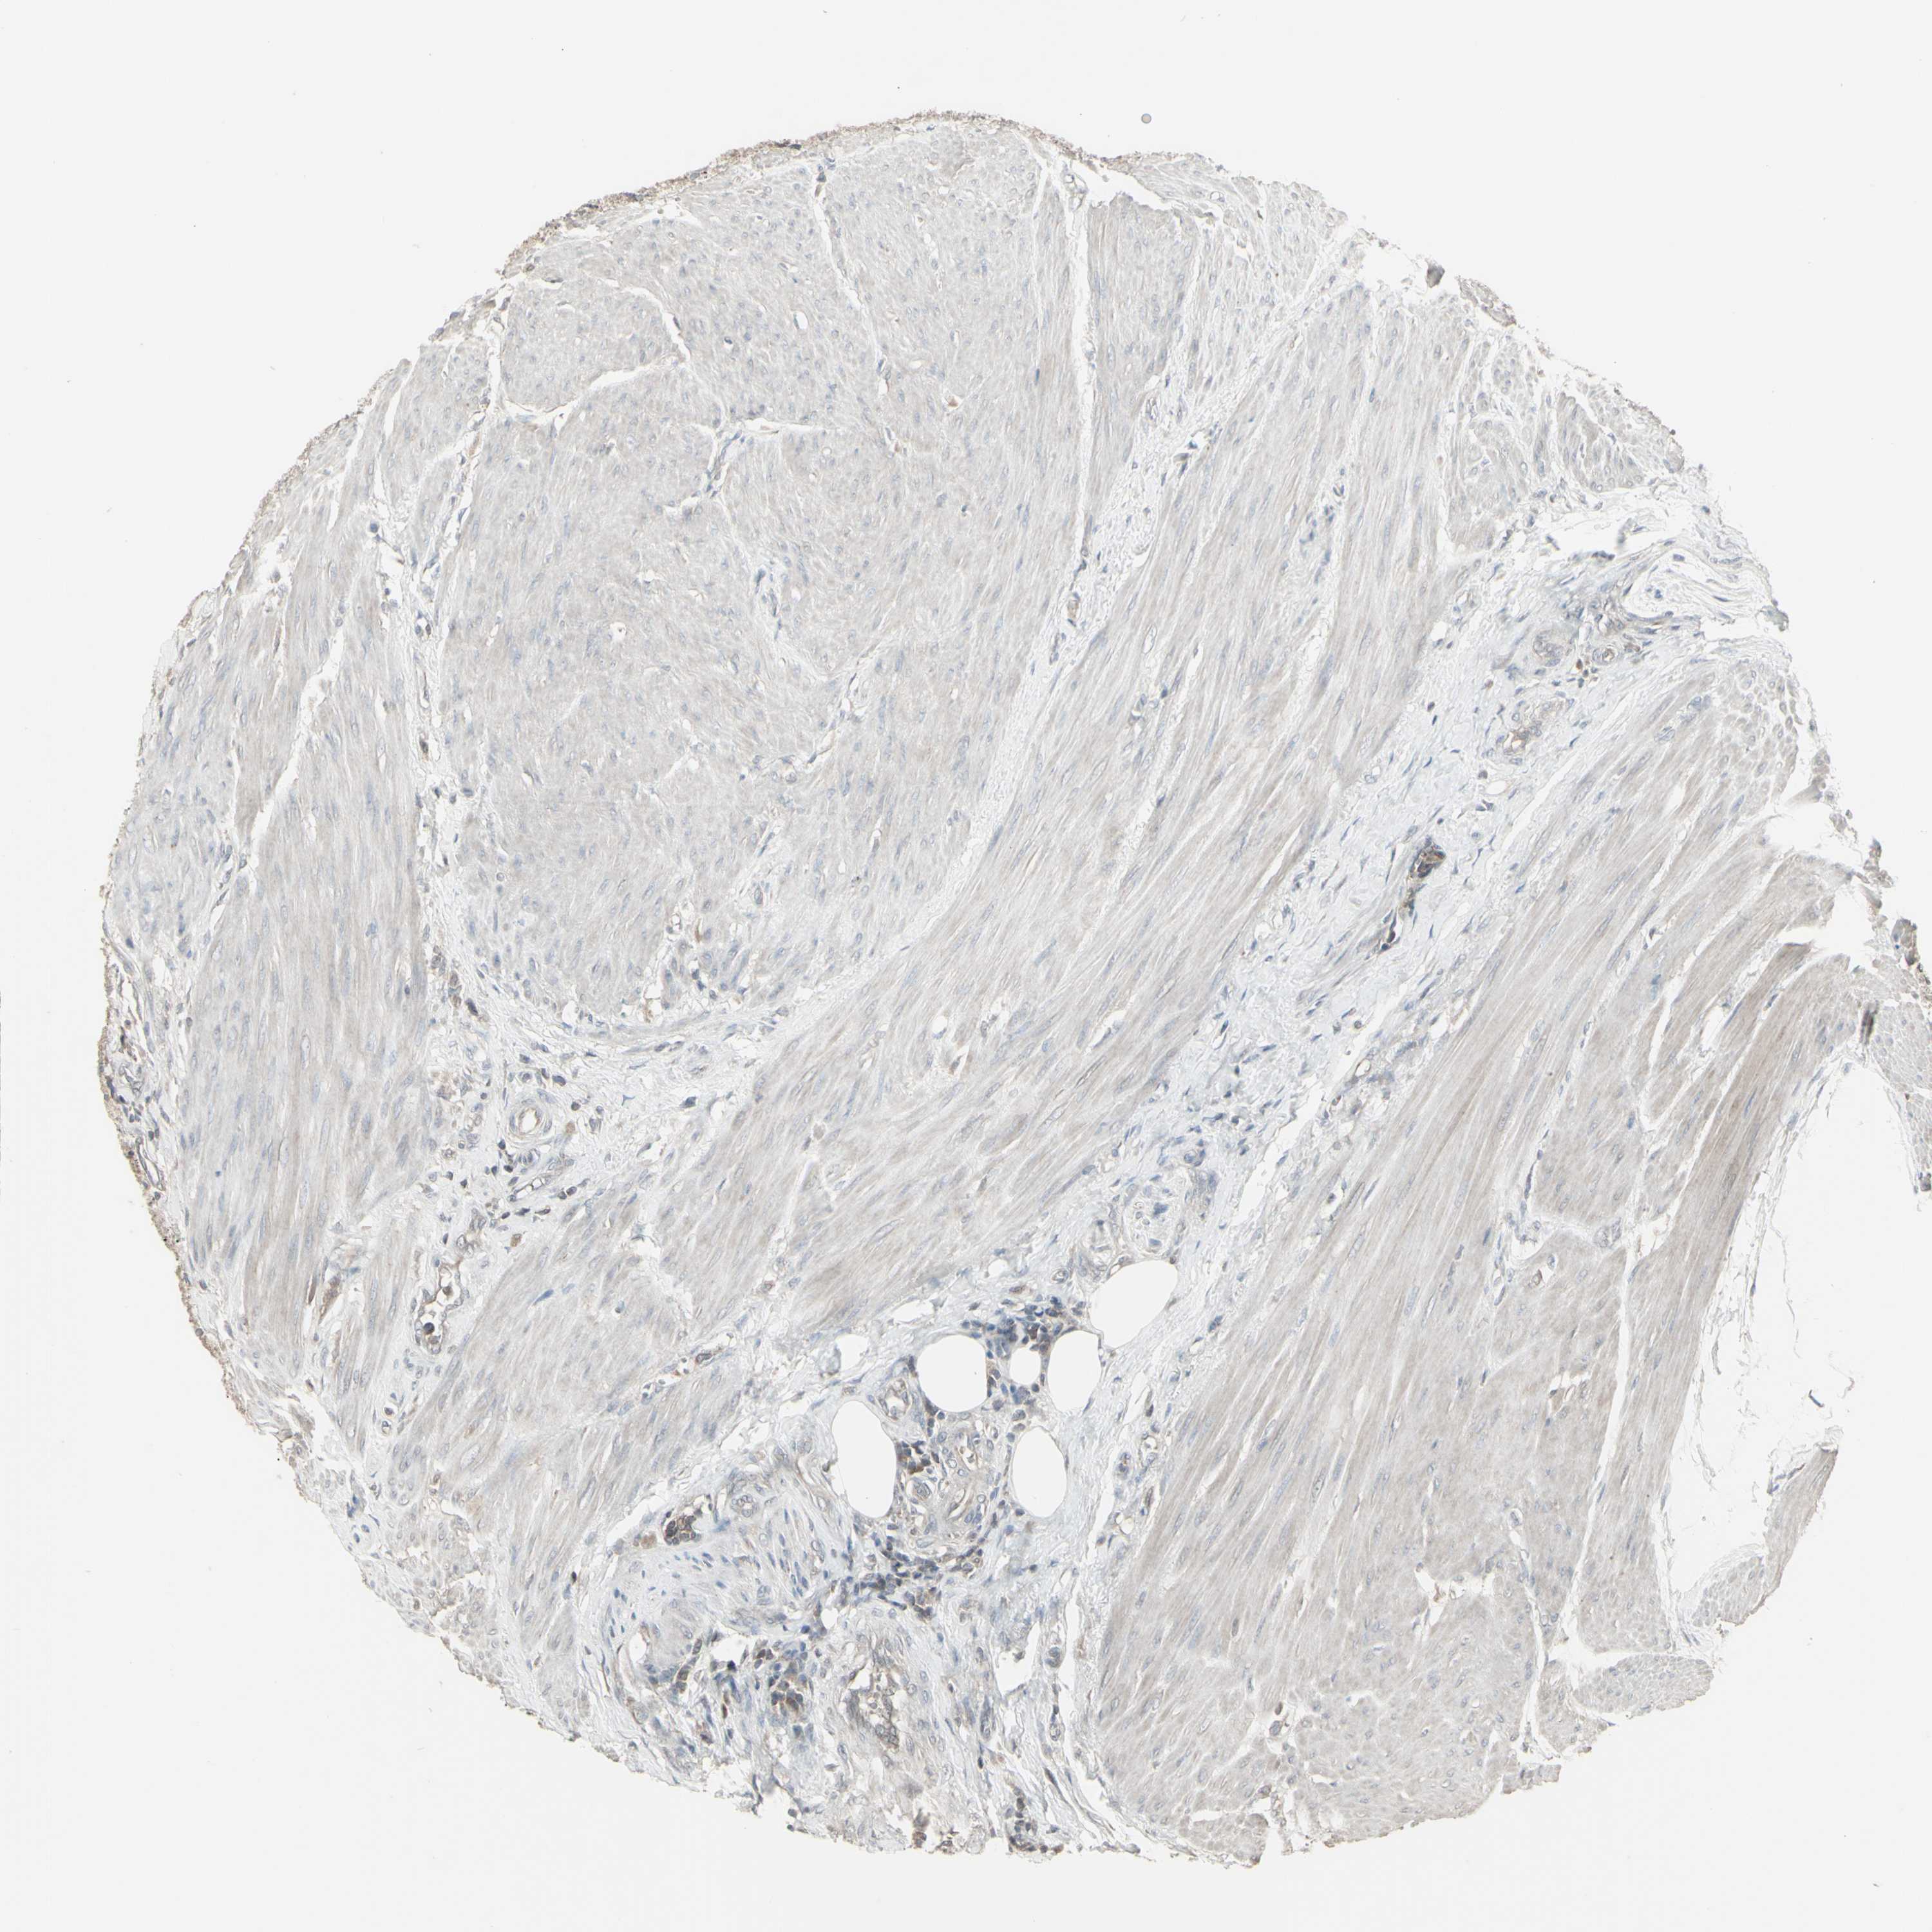

UROTHELIAL CANCER - Protein expressioni

A mouse-over function shows sample information and annotation data. Click on an image to view it in a full screen mode. Samples can be filtered based on level of antibody staining by selecting one or several of the following categories: high, medium, low and not detected. The assay and annotation is described here.

Note that samples used for immunohistochemistry by the Human Protein Atlas do not correspond to samples in the TCGA dataset.

Antibody stainingi

Antibody staining in the annotated cell types in the current human tissue is reported as not detected, low, medium, or high, based on conventional immunohistochemistry profiling in selected tissues. This score is based on the combination of the staining intensity and fraction of stained cells.

Each image is clickable and will lead to virtual microscopy that enables deeper exploration of all samples and also displays staining intensity scores, fraction scores and subcellular localization as well as patient and tissue information for each sample.

Antibody HPA026488

Antibody HPA028425

Antibody CAB011203

Staining

High

Medium

Low

Not detected

Intensity

Strong

Moderate

Weak

Negative

Quantity

>75%

75%-25%

<25%

None

Location

Nuclear

Cytoplasmic/membranous

Cytoplasmic/membranous,nuclear

Urothelial carcinoma, Low grade

Urothelial carcinoma, High grade